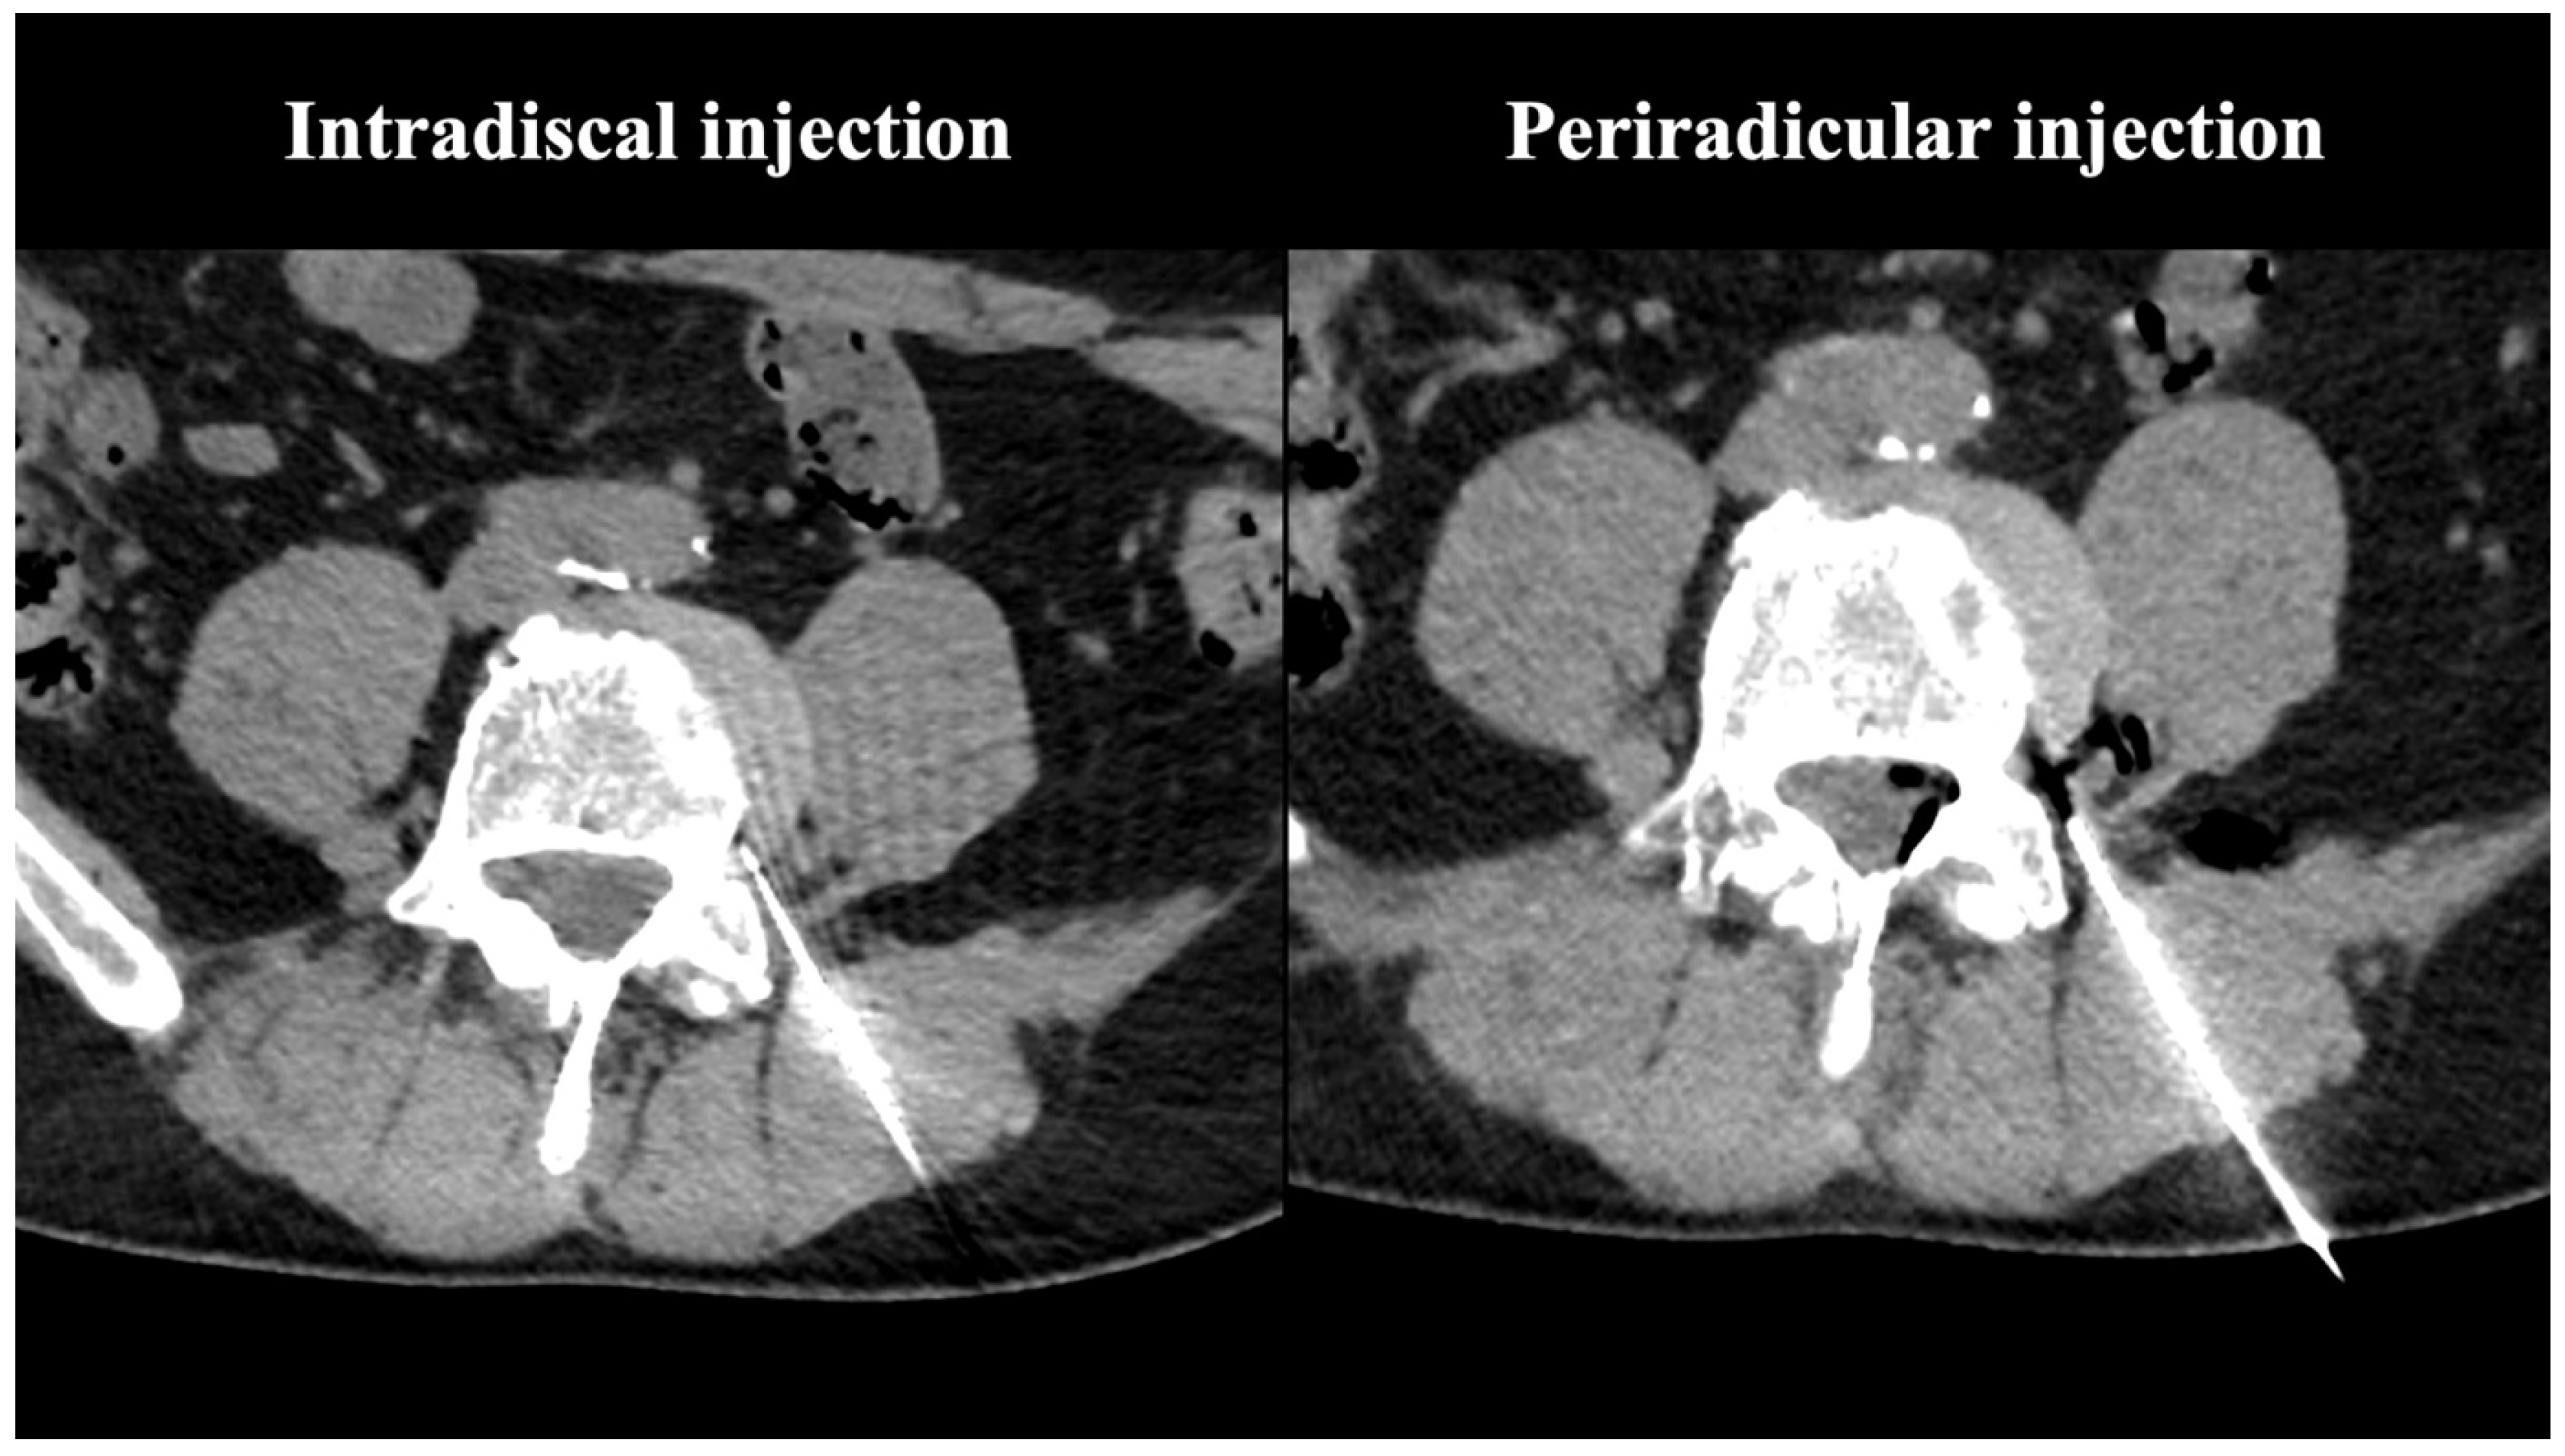

- Muto, M.; Andreula, C.; Leonardi, M. Treatment of herniated lumbar disc by intradiscal and intraforaminal oxygen-ozone (O2-O3) injection. J. Neuroradiol. 2004, 31, 183–189. [Google Scholar] [CrossRef] [PubMed]

- Giurazza, F.; Guarnieri, G.; Murphy, K.J.; Muto, M. Intradiscal O2O3: Rationale, Injection Technique, Short- and Long-term Outcomes for the Treatment of Low Back Pain Due to Disc Herniation. Can. Assoc. Radiol. J. 2017, 68, 171–177. [Google Scholar] [CrossRef]